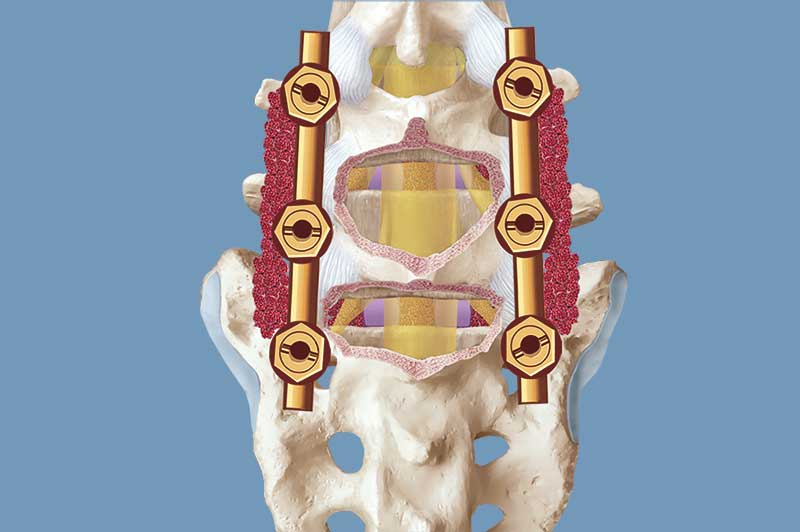

- Titanschrauben werden präzise in die Wirbelkörper eingebracht und mit Längsstangen verbunden

- Zur Versteifung wird Knochenmaterial auf den Querfortsätzen der Wirbelkörper und zwischen den Facettengelenken (Gelenke, die die Wirbelkörper verbinden) angelagert

Stabilisation der Wirbelsäule mit Titanschrauben und Knochenanlagerungen. Erweiterter Spinalkanal, um komprimierte Nerven freizulegen.

Zur zusätzlichen Stabilisation werden in vielen Fällen sogenannte Cages (Titankörbchen) mit Knochenmaterial in den Bandscheibenraum eingesetzt. Dieser Eingriff kann ebenfalls rückseitig oder über einen zusätzlichen seitlichen bzw. vorderen Zugang erfolgen.

Zusätzliche Stabilisation der Wirbelsäule durch Implantation von Cages zwischen den Wirbelkörpern